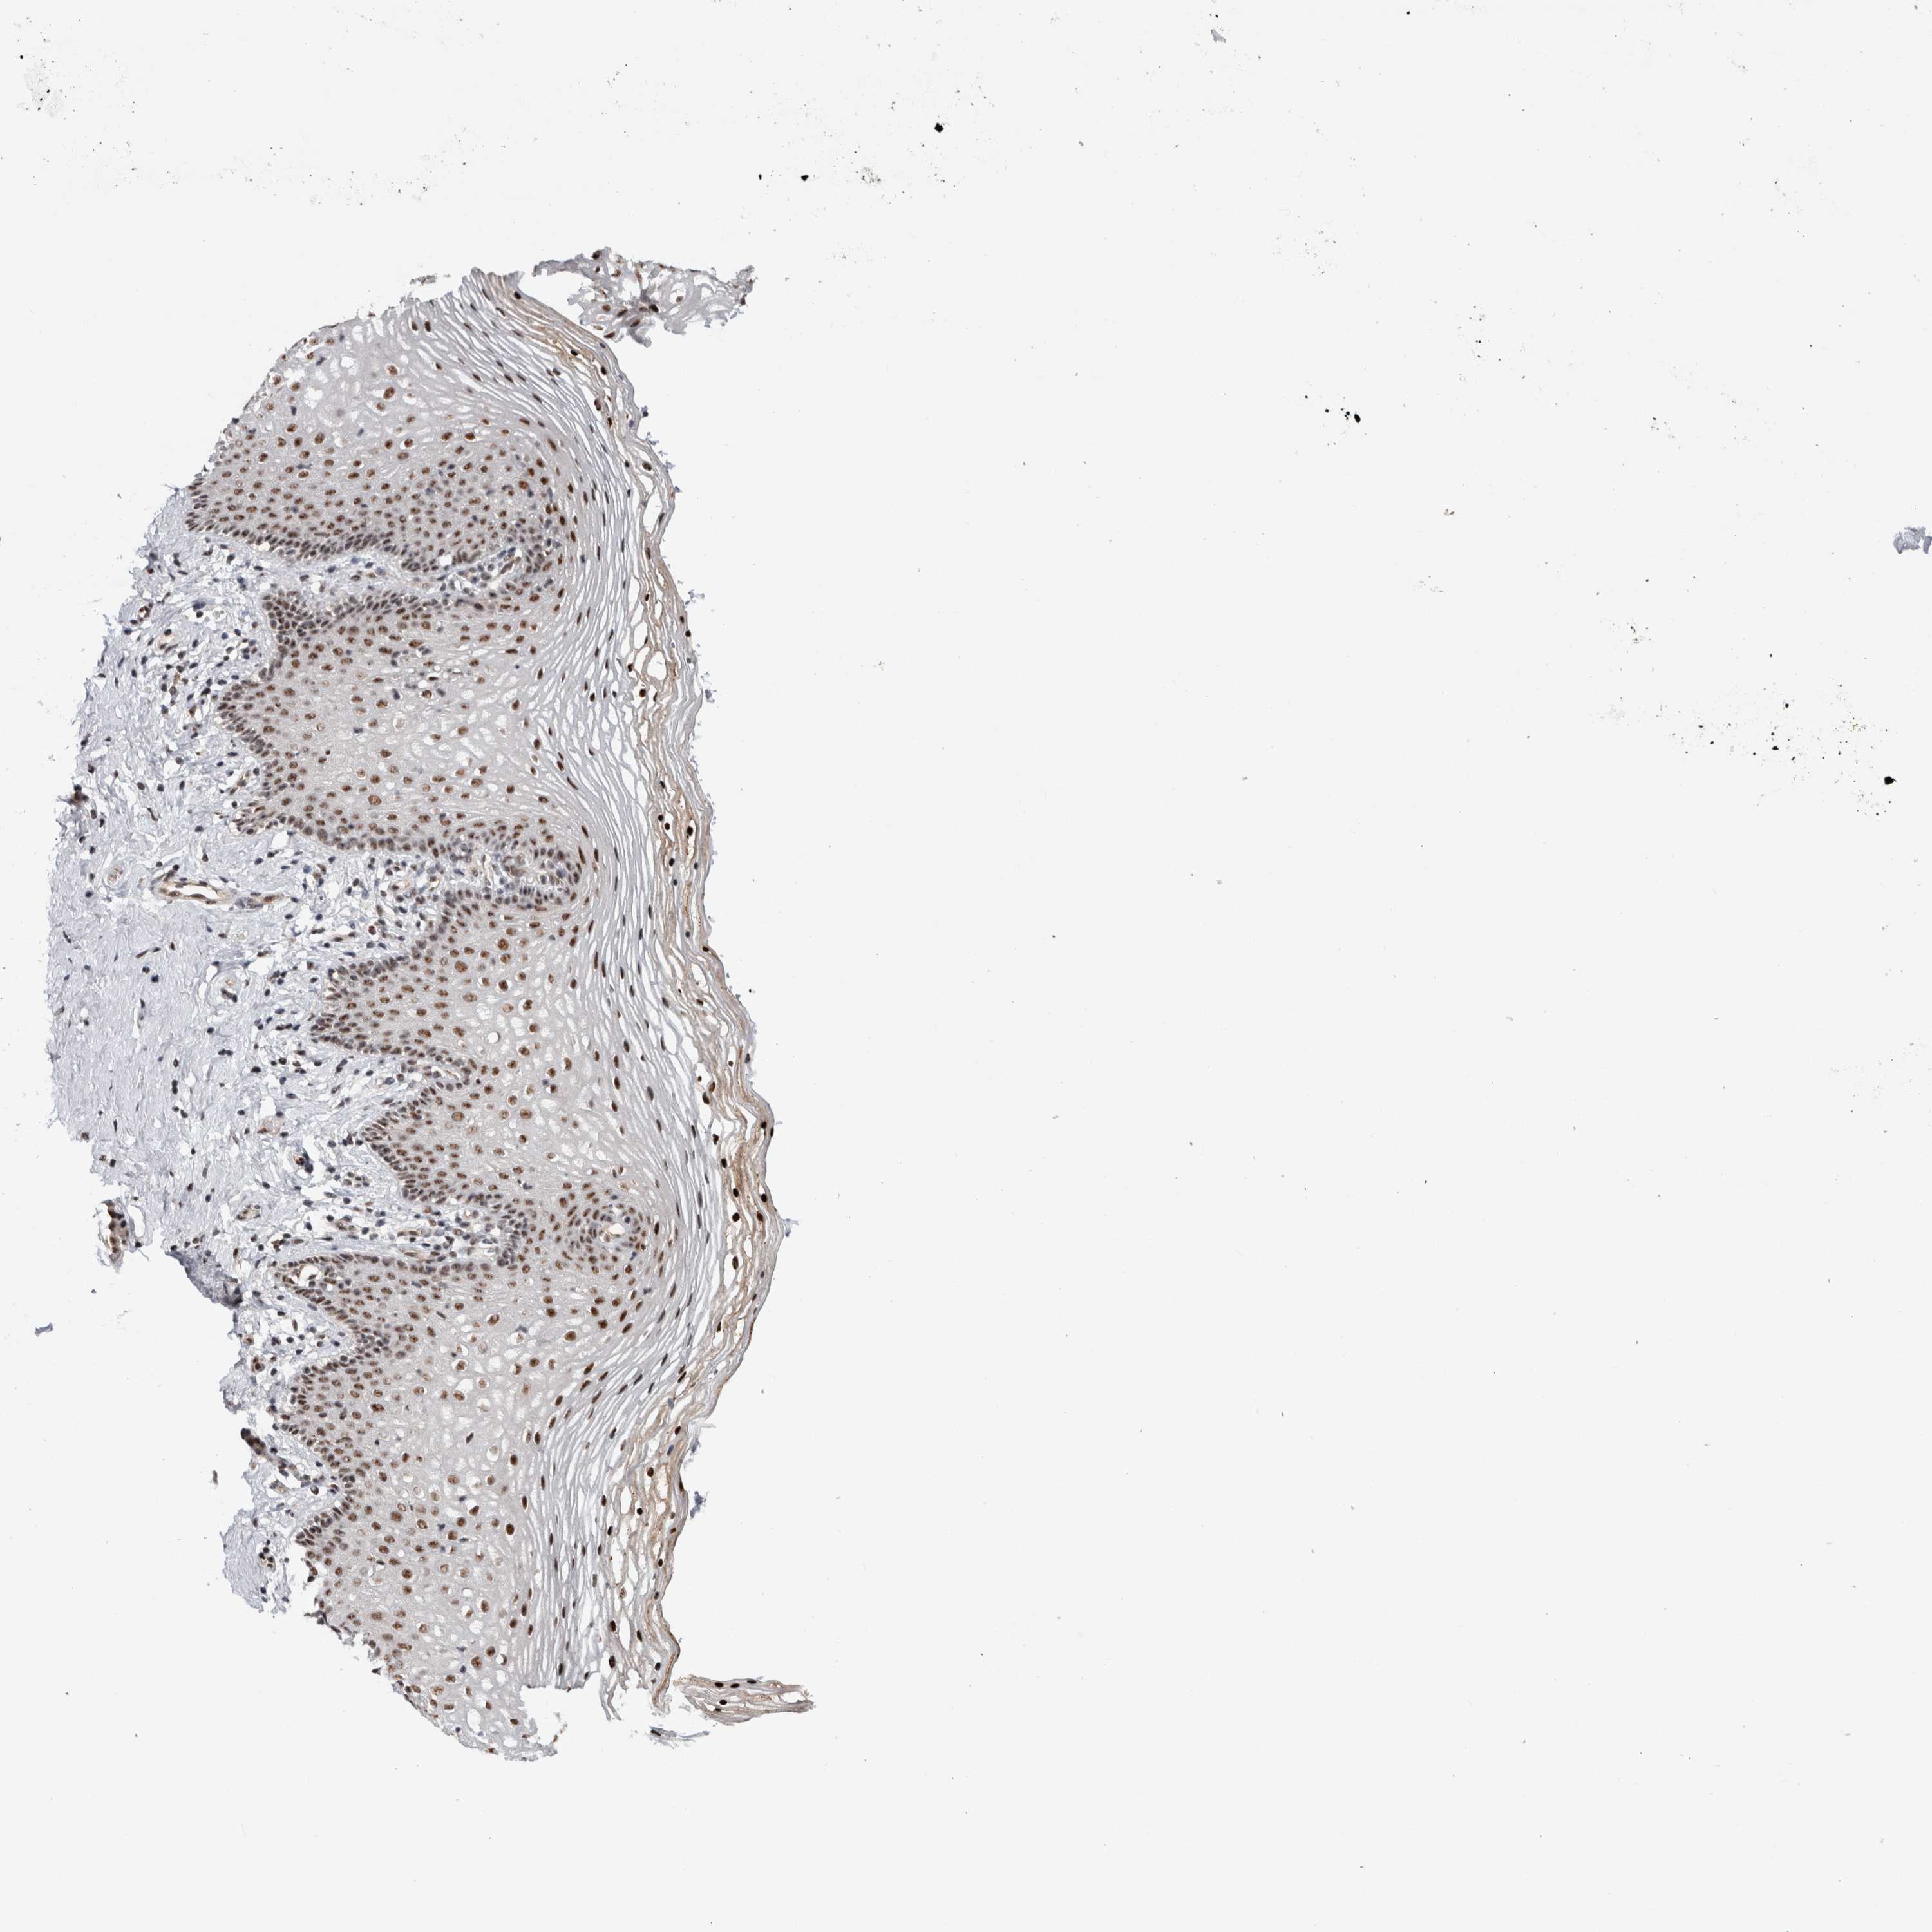

VAGINA - Antibody stainingi

Antibody staining in the annotated cell types in the current human tissue is reported as not detected, low, medium, or high, based on conventional immunohistochemistry profiling in selected tissues. This score is based on the combination of the staining intensity and fraction of stained cells.

Each image is clickable and will lead to virtual microscopy that enables deeper exploration of all samples and also displays staining intensity scores, fraction scores and subcellular localization as well as patient and tissue information for each sample.

Antibody CAB027355Antibody CAB037310

Squamous epithelial cells HighMedium